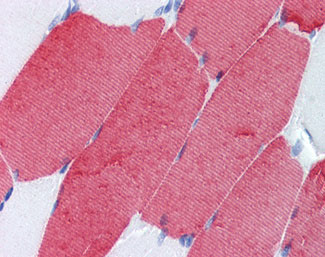

Anti-TNNT3 antibody IHC of human skeletal muscle. |